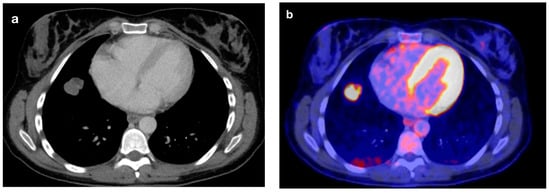

3.2. DECT Image Analysis